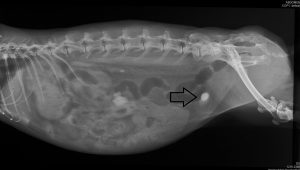

Im Röntgenbild ist beispielsweise deutlich ein heller Blasenstein zu erkennen, also eine Aufhellung. Würde man den Blasenstein jedoch nicht auf einem Röntgenbild sehen, sondern in der Hand halten, wäre er dunkel.

Der Bauchraum wird bei allen möglichen Verdauungsproblemen geröntgt, da z.B. das Ausmaß von Aufgasungen allein durch Abtasten oft nicht zuverlässig eingeschätzt werden kann. Besonders wichtig ist ein Röntgenbild hier, um sicher eine Aufgasung von einer Magenüberladung unterscheiden zu können – denn je nachdem, was vorliegt, ist die folgende Vorgehensweise sehr unterschiedlich und es ist lebenswichtig, dass hier richtig unterschieden wird. Auch muss bei Tumoren im Bauchraum röntgenologisch ausgeschlossen werden, dass Metastasten vorliegen. Bei Verdacht auf eine Blasenentzündung sollte ebenfalls ein Röntgenbild angefertigt werden, um auszuschließen, dass sich Ablagerungen in der Blase befinden, die dem Kaninchen Schmerzen verursachen. Auch eventuelle Vergrößerungen der Gebärmutter werden über ein Röntgenbild festgestellt.